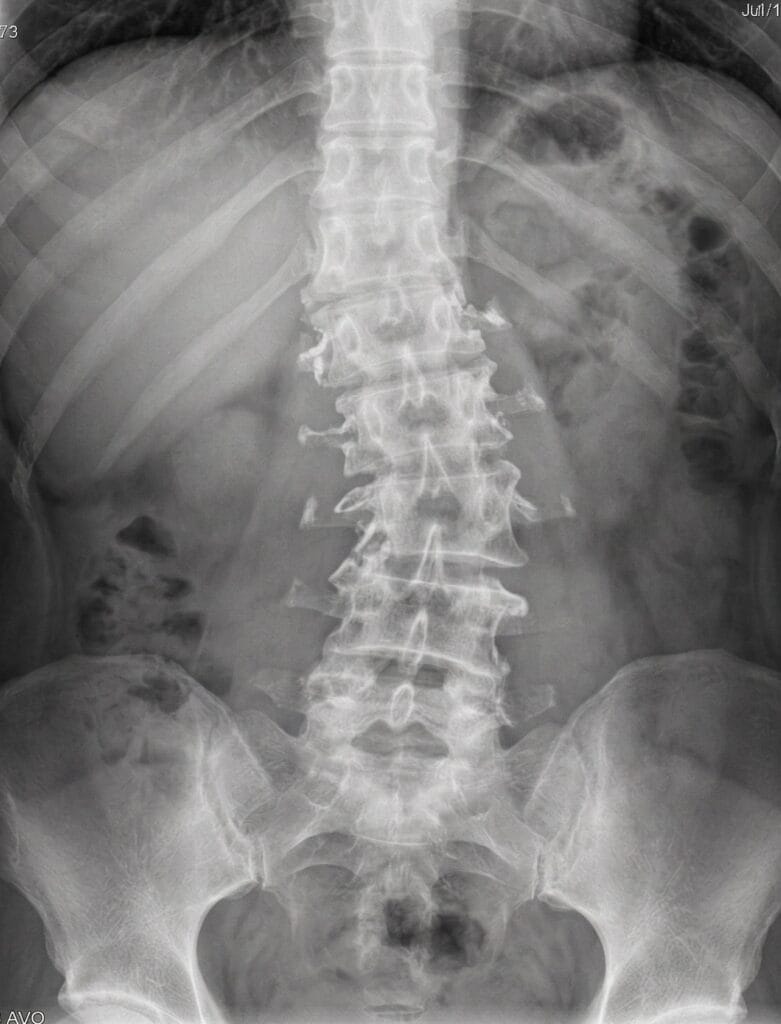

- الجنف التنكسي (Degenerative Scoliosis): هذا النوع يظهر لاحقاً في الحياة (غالباً بعد سن الخمسين). ويحدث نتيجة التآكل والخشونة غير المتساوية في الغضاريف ومفاصل العمود الفقري السفلية، مما يتسبب في ميلان الفقرات تدريجياً (موضح في هذه الصورة).

- نبدأ بدراسة صور الأشعة السينية (X-rays) الخاصة بك بعناية فائقة لتحديد زوايا الانحناء واتجاه الالتواء.